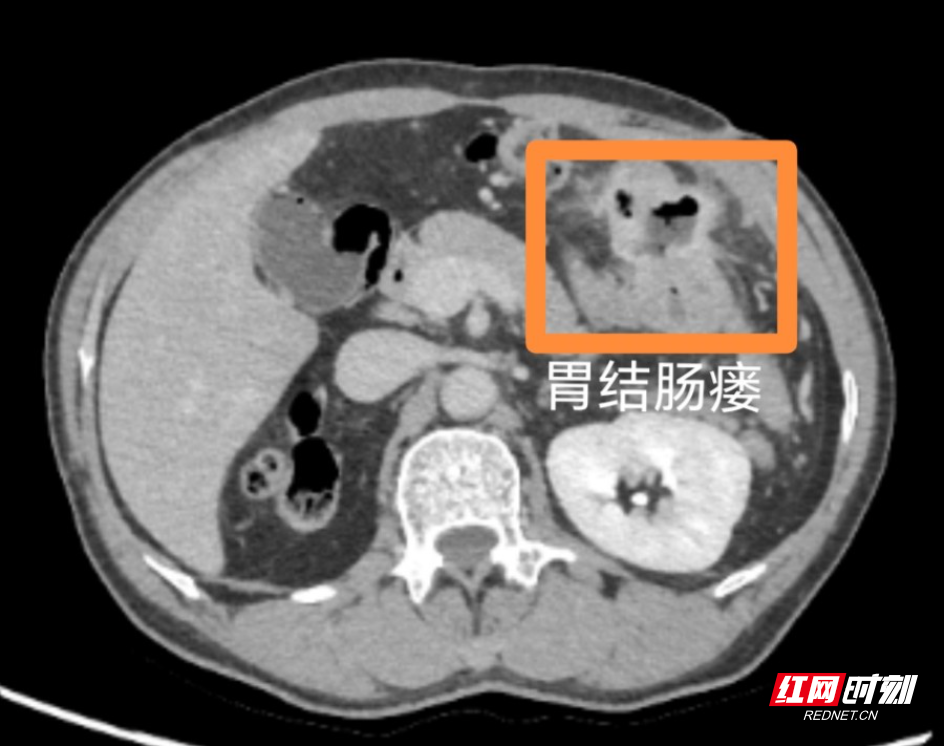

入院后,经胃镜、肠镜、腹部CT等检查,患者被确诊为胃结肠瘘。因胃与结肠之间形成异常通道,食物未经充分消化直接进入大肠,导致严重营养不良。然而,患者既往有胃大部切除术(毕II式吻合)、肾切除术病史,腹腔正常解剖结构已被破坏,加之长期感染与手术影响,腹腔脏器粘连极为严重,局部组织水肿脆弱,手术风险高、操作难度大。